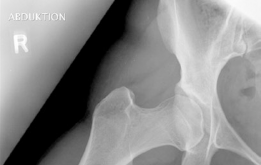

The most critical functional radiograph in our preoperative workup is the AP Abduction view (often taken with the hip in 20-30 degrees of abduction and slight internal rotation). This view simulates the mechanical effect of a periacetabular osteotomy by effectively "rotating" the femoral head deeper into the acetabular dome. In this patient's case, the abduction view demonstrates excellent achievable congruency and congruity. The joint space becomes symmetric, and the femoral head centralizes perfectly within the socket. This is the ultimate litmus test for joint preservation: if the abduction view shows persistent incongruency or a "hinging" effect where the joint space narrows medially, a reorientation osteotomy may be contraindicated, as it would simply rotate a misshapen socket over a misshapen head, accelerating arthrosis.